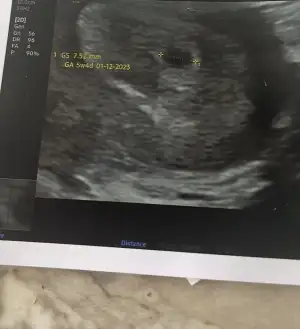

Ben anlamıyorum canım ama daha önce birkaç yerde okumuştum ramzi teorisi diye bişey var bebeğin kesenin içindeki konumuna göre cinsiyet tahmini yapıyorlar ve vajinal veya karından ultrasona göre değişiyor. Vajinal ultrason ise bebek kesenin sağında ise erkek solunda ise kızmış. Karından ultrasonda da bebek kesede sağda ise kız solda ise erkekmis. 6ile 8.haftalarda bakiliyormus. Hatta çok merak etmiştim okuduğumda

ve kızımın ultrason görüntüsüne bakmıştım gerçekten tutuyormu diye 6.haftalarda varmış ilk ultrasonumuz karından baktım gerçekten de bebek sağ tarafta duruyordu aaa tutuyormu acaba olmuştum yani

tutmuştu simdi de tutarmi bilmiyorum daha bebeğimi göremedim tam nerde olduğunu. Tabi ki de rabbim bilir belki de tesadüf ama tutanlar varmış